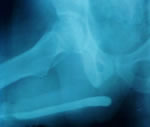

Контрольная восходящая уретрограмма – уретра

проходима на всем протяжении. |